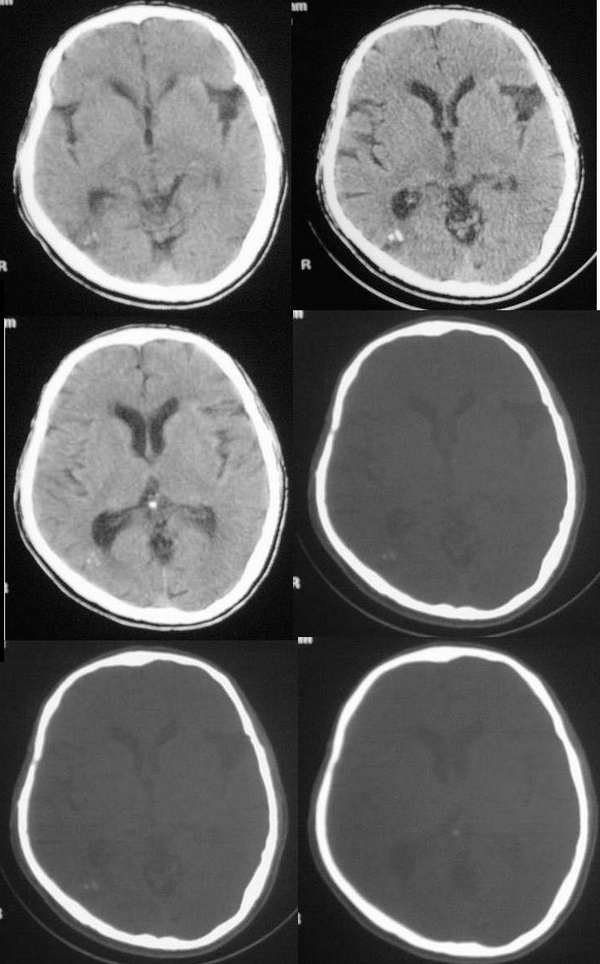

病人 男 58岁 作上下肢麻木

右侧颞叶枕部见斑点状高密度影,其外侧脑组织见小片状低密度,右侧脑室三角部略大,无占位效应,颅板结构正常,左侧侧裂池增宽,考虑1)右侧颞叶枕区血管畸形 2)局限性脑萎缩.

ct所见:右侧颞枕叶见斑点状高密度影,其外侧脑组织见小片状略低密度区,同侧脑室三角部略扩大,中线结构居中,颅板结构完整。考虑 :1、右侧颞枕叶脑血管畸形 ,建议增强扫描或mr作进一步检查。

右侧枕叶可见局限性混杂密度的影,其中可见散在的点状和条状的钙化影,周边可见

略低密度影。局部脑组织无受压移位,而且临近侧脑室三角部略扩大。局部枕骨与

对侧的对比好象无明显差异

临床表现仅仅是上下肢麻木

1avm

2sturge-weber综合征和海绵状血管瘤

3脑囊虫